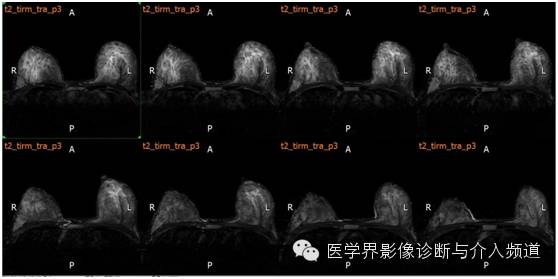

MR平扫及增强示:双乳表面皮肤光整,乳头无凹陷,皮下层次清晰,双乳腺体较丰富,右乳外上象限近胸壁处可见不规则样团状等T1异常信号,FS-T2WI呈高信号,DWI(b=800)示病灶呈略高信号,ADC图呈略低信号,边界不清,并沿导管浸润,范围约4.8×2.5×6.6 cm,双乳内见多发片状、结节样等T1略长T2异常信号。注入GD-DTPA后,上述病灶强化呈”平台”型。右侧胸骨后及腋窝见多发淋巴结影,较大者位于右侧腋窝,最大径约0.8 cm。